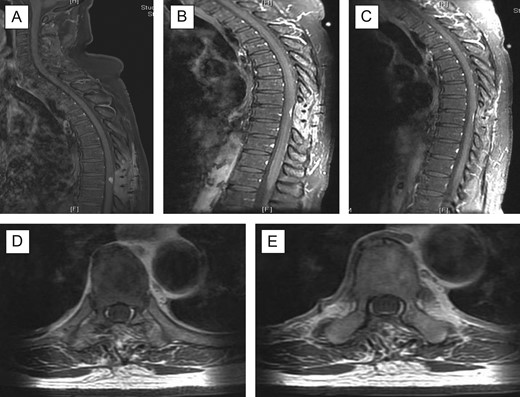

A decision was taken to operate the patient in view of cord compression, progressive neurological deterioration and for histopathology confirmation of the diagnosis. A T8/T9 laminectomy and excision of intradural extramedullary lesion was performed. The tumour was grossly reddish in colour; located purely extramedullary and near total excision was performed. Post-operatively, patient had MRI cervical spine, MRI brain with contrast and CT thorax, abdomen, pelvis for further evaluation of the disease; scans were unremarkable with no evidence of primary source/ metastatic lesions. The pain improved significantly, lower limb power improved and patient was subsequently transferred to rehabilitation centre to optimise recovery to achieve mobility independence. Twelve-month follow-up at clinic revealed significant improvement in back pain and in bilateral lower limb power, with no evidence of recurrence. Repeat MRI scans showed interval improvement of the disease (Fig. 2). Patient remained in rehabilitation unit and was discharged home after 6 months.

Post-operative follow-up MRI scan. There is residual focus of dural thickening and enhancement at the level T9 which demonstrated further reduction in prominence (A–C); there is resolution of the cord oedema and no new enhancing lesion is seen in the spinal canal; (A) sagittal with contrast 3 months’ follow-up; (B) 6 months’ follow-up; (C) 11 months’ follow-up; (D + E) axial views with contrast 11 months’ follow-up at T9 level.

In our case, MRI spine with contrast was initially suggestive of an intramedullary involvement from an intradural extramedullary lesion. However, intraoperatively, the lesion appeared grossly extramedullary; subtotal excision of the lesion was performed as it was adhered very closely to the spinal cord. Pre-operative embolization was not done; we did not start chemotherapy too as there were no evidence of metastases. Following 6 months from operation, we offered radiotherapy as adjuvant for patient however he declined it because his symptoms were improving following rehabilitation therapy. His follow-up scans also showed further reduction of cord oedema and residual of the lesion. In view of these, he opted for conservative management with a 6-month follow-up scan. The latest scan (11 months post-operative) showed interval regression of cord oedema and no new enhancing lesions were seen (Fig. 2c). There was also no evidence of recurrence and metastasis of disease following 12 months. Gold standard for diagnosis is histological studies, mainstay treatment for HPC would be surgical resection with radiotherapy if residual disease present post-operatively or chemotherapy in event of metastasis. Close and regular long term follow-up (at least 6 monthly) is recommended for HPC in view of its malignant and recurrence potential [11].